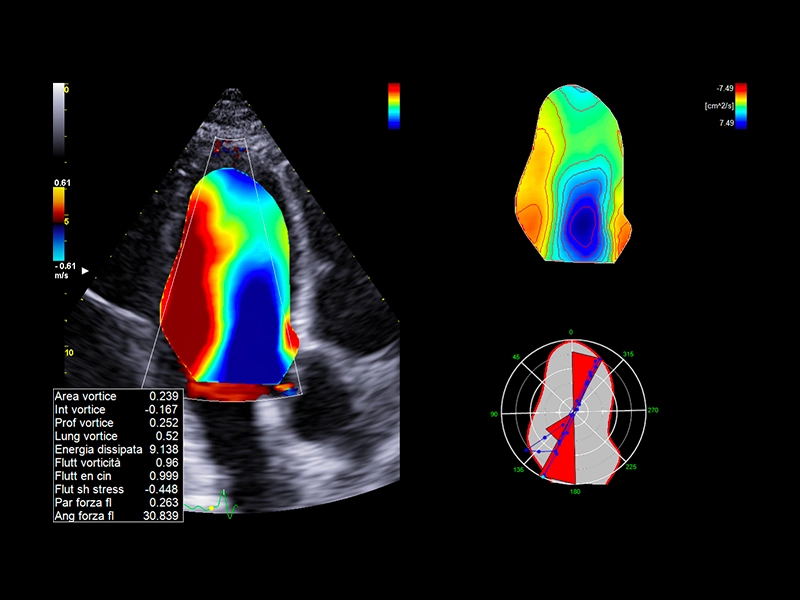

MyLab™A70 - AutoCM

MyLab™A70 - AutoCM